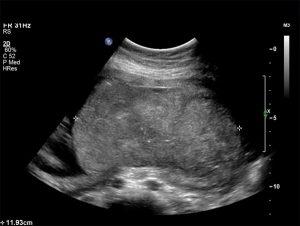

This course focuses on the sonographic evaluation of the normal and abnormal placenta, offering insights into placental development, morphology, and pathologies. Placental conditions such as previa, accreta, abruption, and chorioangiomas are examined, with emphasis on the role of ultrasound in detecting these abnormalities. The course includes specific techniques for identifying various placental conditions, including the use of color Doppler to assess blood flow in lesions like chorioangiomas and to detect complications such as fetal hydrops or polyhydramnios. It also covers the impact of placental abnormalities on fetal development, especially in cases like intrauterine growth restriction (IUGR). The curriculum also highlights the relationship between placental dysfunction and common complications in pregnancy, such as preeclampsia and elevated maternal serum alpha-fetoprotein levels.

Apply diagnostic ultrasound to identify placenta previa, abruption and other abnormalities that are the potential source of fetal disease and / or compromise.